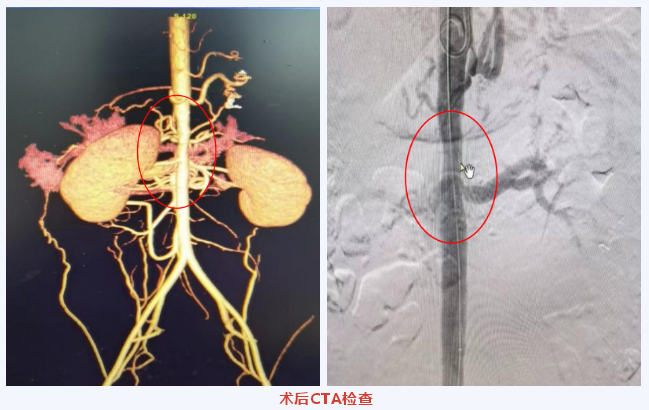

术中可见腹主动脉肾动脉分支水平及以上严重狭窄,依次使用直径8mm、12mm球囊导管逐渐扩张后,术中复查造影显示腹主动脉狭窄处管腔获得良好,未见明显夹层及血肿,出院前复查胸腹主动脉CTA提示残余狭窄处管腔直径达11mm左右,较前明显改善。

术后患者血压通过药物治疗维持稳定,监测血压120/70mmHg左右,于2023年3月15日顺利出院。